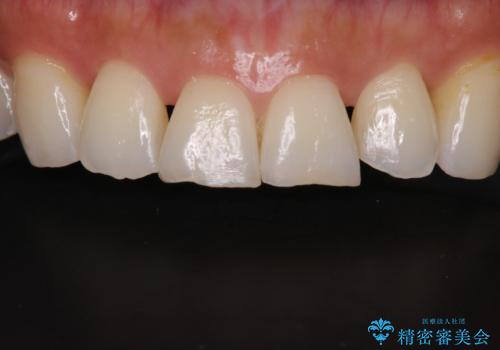

前歯の形気になる セラミッククラウン(SP)

- 矯正終了した患者様で、前歯の形が気になるということで

セラミッククラウンにて治療された方の症例です。

患者様と何度か修正を加えながら歯の形、色に満足していただけました。